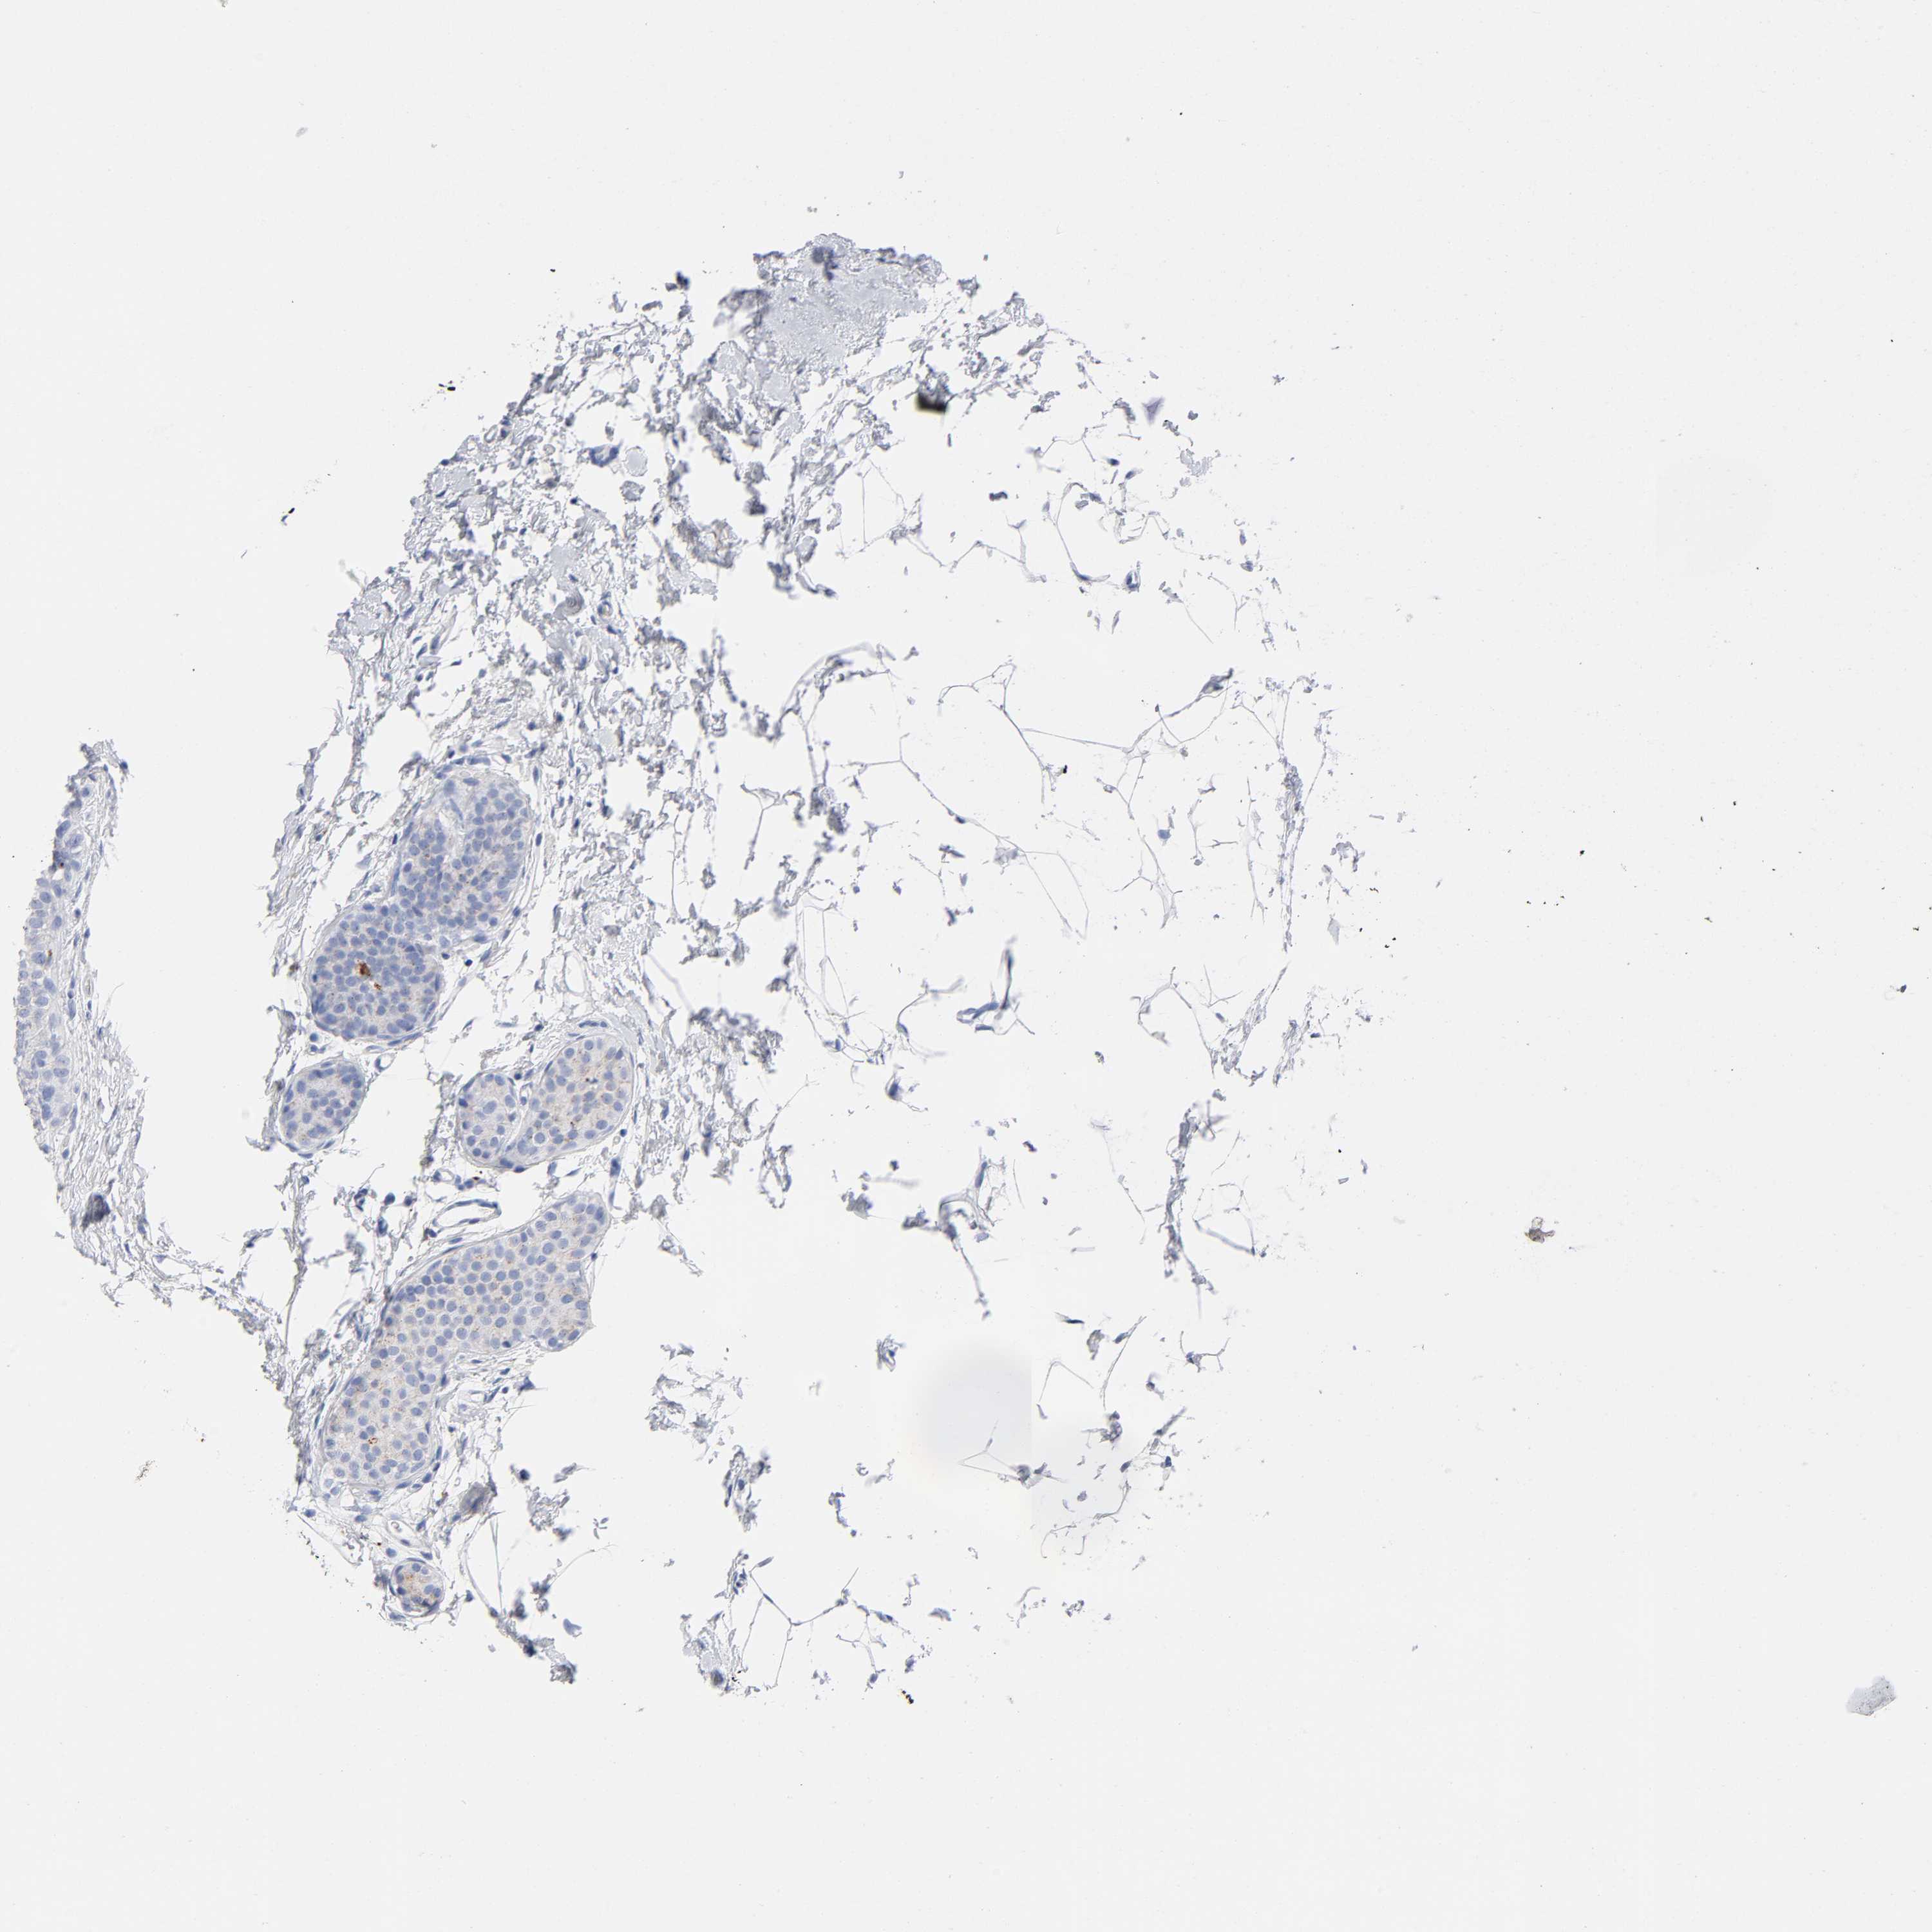

BRCA TCGA BRCA VALIDATION PROTEIN EXPRESSION

ANTIBODIES

AND

VALIDATION